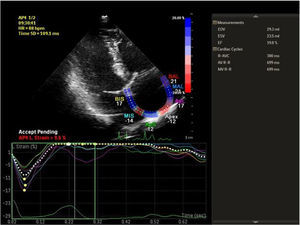

Speckle tracking analysis was performed by a single experienced and independent investigator (OO) who was blinded to the clinical data, using commercially available semiautomated 2D wall motion tracking software (Philips Healthcare Systems). To assess RA myocardial function, the RA endocardium was manually traced when the right atrium was at its maximum volume, just before tricuspid valve opening, as identified in apical 4-chamber view. The RA basal septal, basal lateral and apical borders were manually traced, followed by automatic tracing of the endocardial and epicardial borders, thus delineating a region of interest composed of six segments. After analysis of segmental tracking quality and manual adjustment of the region of interest, longitudinal strain curves were generated by the software for each atrial segment. A cine loop preview feature enabled visual confirmation that the internal line followed the movements of the RA endocardium throughout the cardiac cycle. If tracking of the RA endocardium was unsatisfactory, manual adjustments of the region of interest size were performed to ensure optimal tracking (Figure 1). RA longitudinal strain was measured in six segments of the atrium. As previously described, peak RA longitudinal strain at the end of the RA reservoir phase was calculated by averaging the values for all RA segments to yield global RA longitudinal strain.10,12